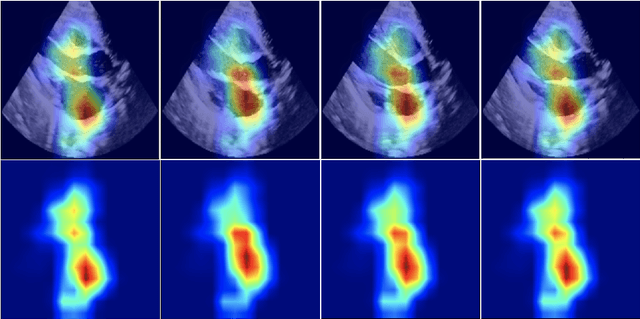

Abstract:Pulmonary hypertension (PH) in newborns and infants is a complex condition associated with several pulmonary, cardiac, and systemic diseases contributing to morbidity and mortality. Therefore, accurate and early detection of PH is crucial for successful management. Using echocardiography, the primary diagnostic tool in pediatrics, human assessment is both time-consuming and expertise-demanding, raising the need for an automated approach. In this work, we present an interpretable multi-view video-based deep learning approach to predict PH for a cohort of 194 newborns using echocardiograms. We use spatio-temporal convolutional architectures for the prediction of PH from each view, and aggregate the predictions of the different views using majority voting. To the best of our knowledge, this is the first work for an automated assessment of PH in newborns using echocardiograms. Our results show a mean F1-score of 0.84 for severity prediction and 0.92 for binary detection using 10-fold cross-validation. We complement our predictions with saliency maps and show that the learned model focuses on clinically relevant cardiac structures, motivating its usage in clinical practice.